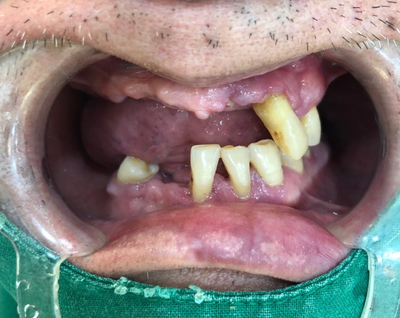

오늘은 임플란트, 조금 더 안아프고 간편하게 할 수 있는 방법에 대해

실제 저희 치과에서 진행한 사례를 통해 알아보고자 합니다.

50대의 나이에도 남은 이가 거의 없는 분입니다.